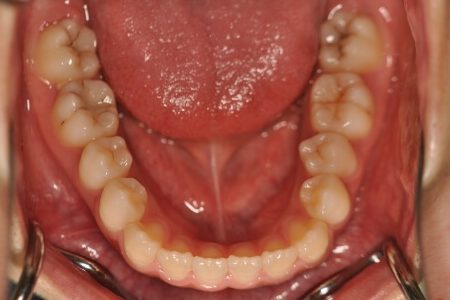

開咬(非抜歯)【2137】

初診時

年齢

15歳 性 別 女性

治療内容の詳細 初診時15歳の女性で、上の歯のがたつき、かみ合わせ、歯の中心のズレ、鼻から下が長いのを気にされ来院されました。

検査の結果、上顎前歯部叢生および開咬を伴うアングルⅠ級不正咬合と診断しました。